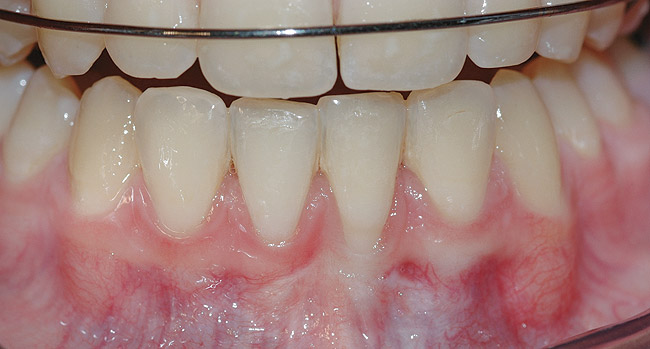

CASE 1 Fig 2. Pre-treatment clinical view of a 28-year-old patient with Miller Class I recession of the lower left central incisor treated with conservative SPT.

Figure 2

Fig 3. Two-year follow-up of same patient shows spontaneous root coverage.

Figure 3